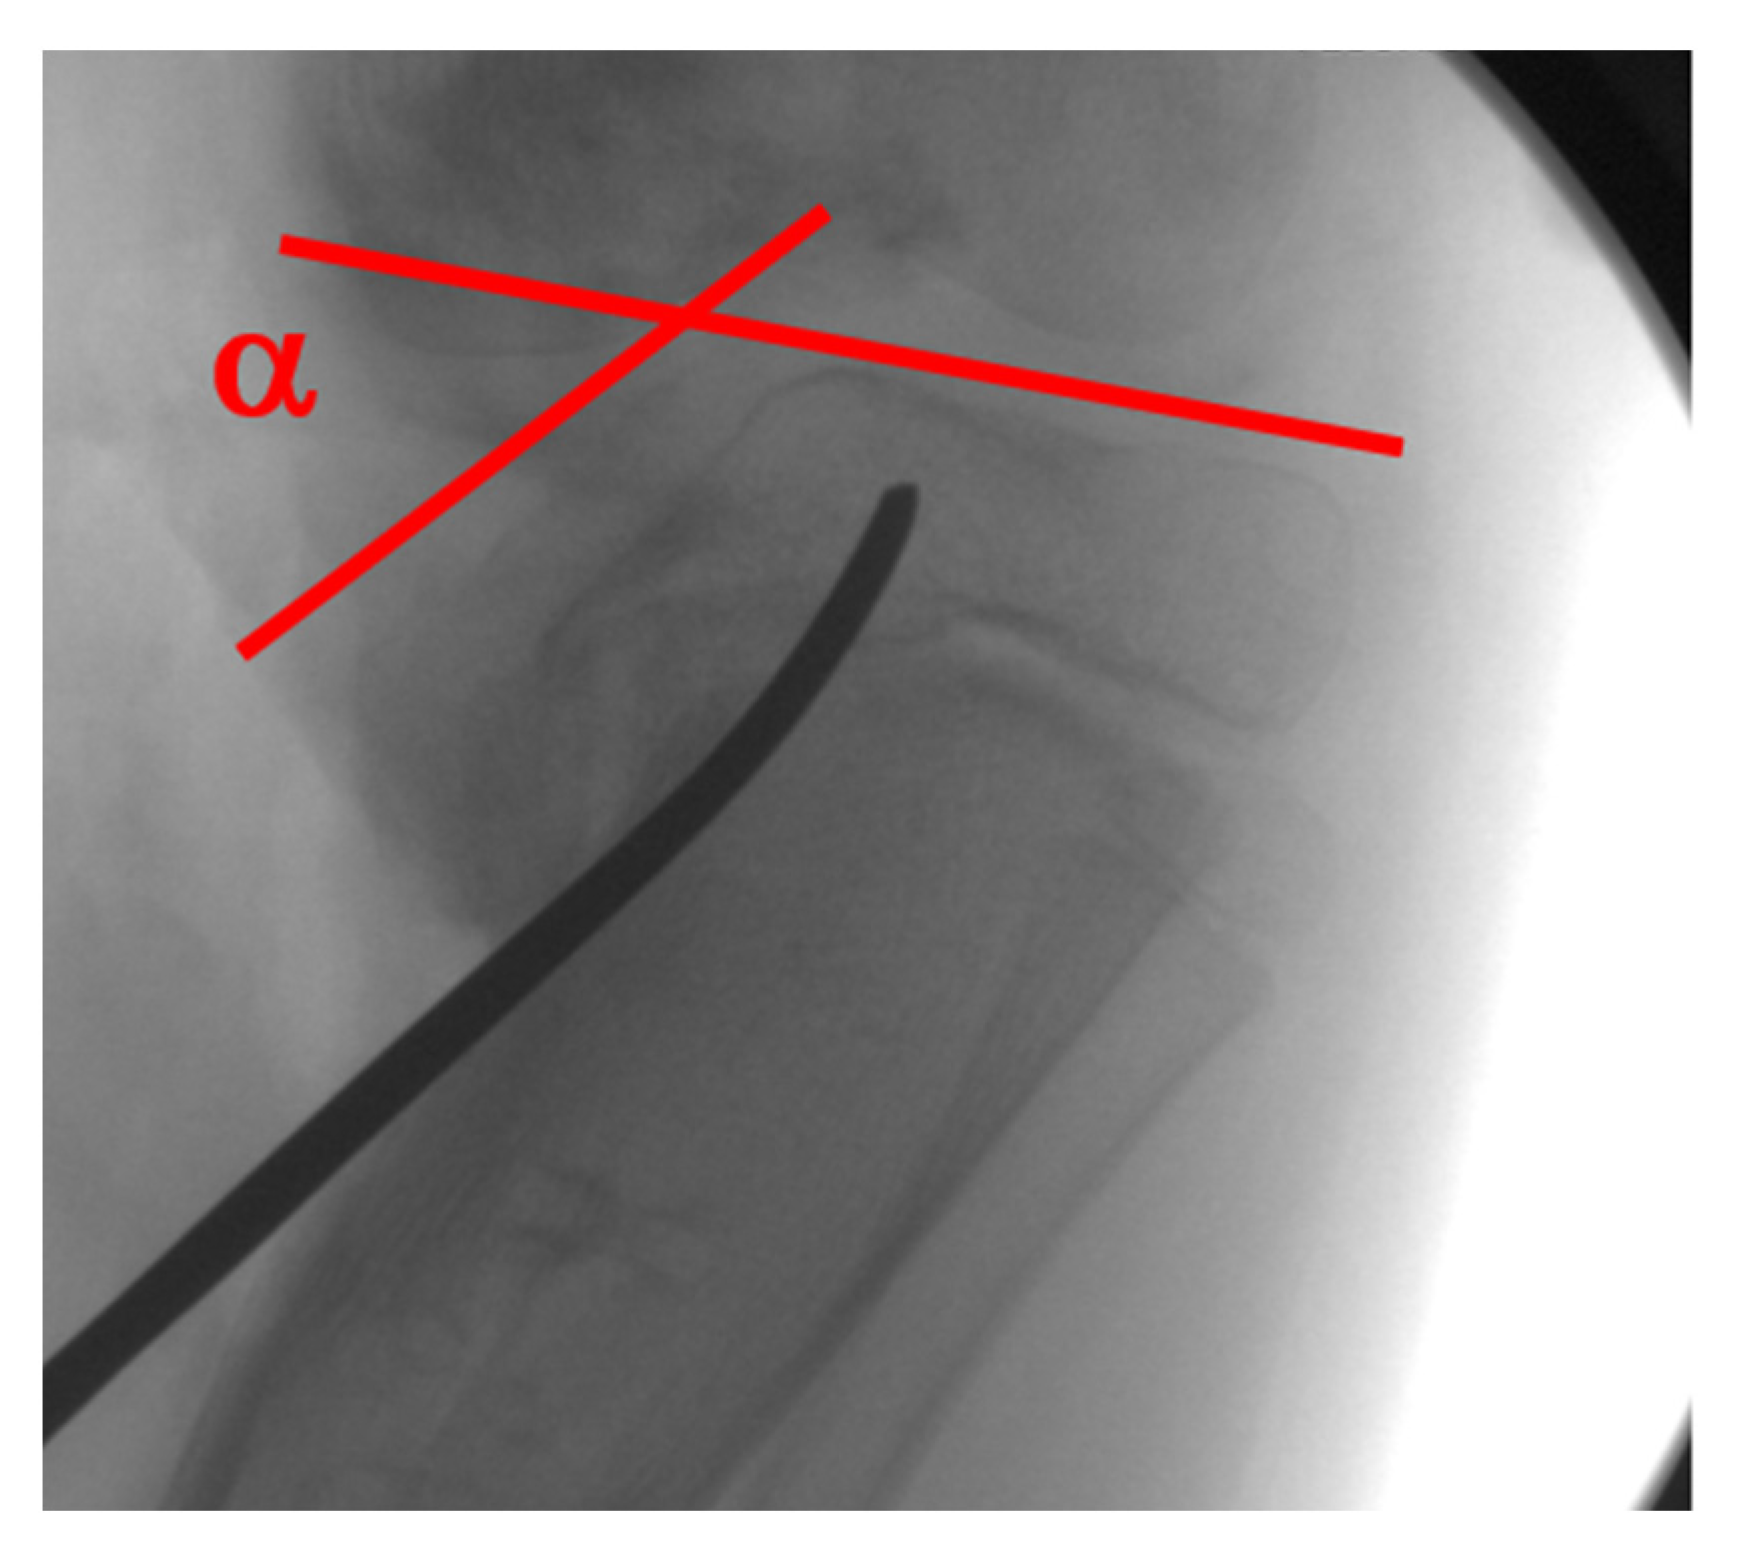

4. Radiographic Imaging

5. Radiographic Analysis